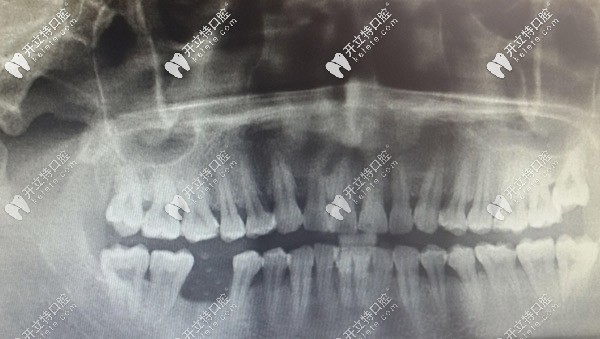

從顧客的曲斷X線片,可以看到右下6的牙槽骨明顯低于相鄰牙齒,已經(jīng)吸收,出現(xiàn)三度松動。右下6也出現(xiàn)了二度松動,勉強(qiáng)保留一定的要和功能。

半個月后來復(fù)診,查看牙窩有膿液溢出,且腫脹沒有消退,決定拍片看。片子顯示右下5有陰影,且陰影有一高密度區(qū),診斷有死骨形成,局麻取出死骨。

之后有來復(fù)診,右下5區(qū)還是腫脹有膿溢出。拍了曲斷牙片后顯示無異常,針對此情況,拍CBCT片顯示右下4根尖有少許陰影,其他都是陰性。